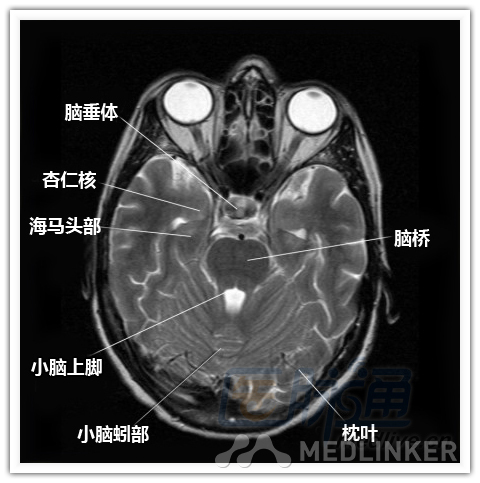

简明易懂的脑部断层解剖:横断位MRI(1)

本文将对不同横断位的脑部MRI图像进行标示,主要讲解内容是脑部基本解剖。脑部横断位解剖,尤其是内囊层面的影像学解剖一直是一大重点,一起来学习一下。 横断位图像顺序:由足侧至头侧 本文转载自医脉通。 声明:本文转载是出于提供更多信息以参考使用或学习、交流之目的,不用于商业用途。转载无意侵犯版权,如转载文章涉及您的权益等问题,请作者速来告知,我们将尽快做删除处理。